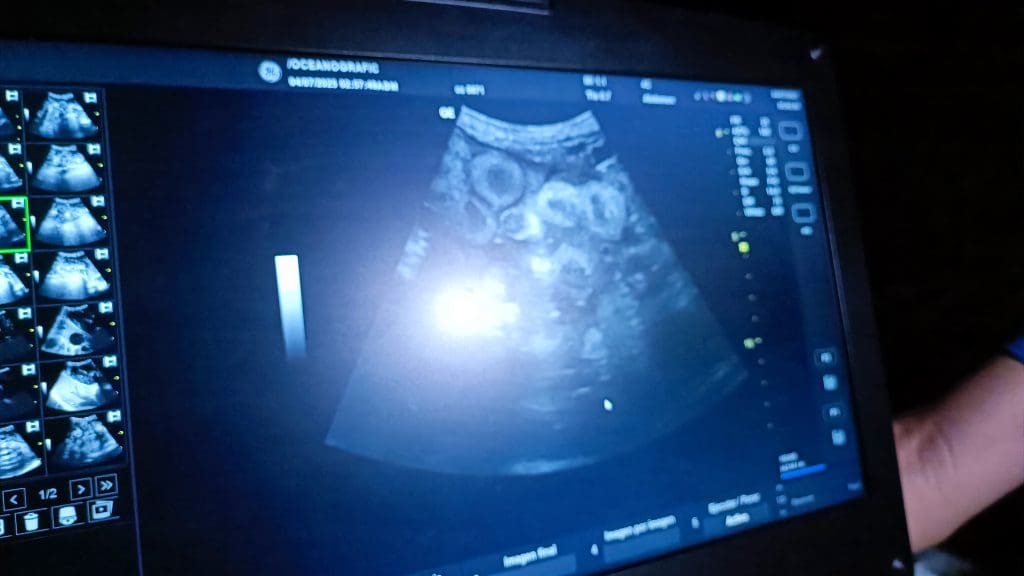

Los especialistas realizaron una ecografía al ejemplar y esta mostró que el animal contenía más huevos en su interior, por lo que en unas semanas podría volver a desovar.